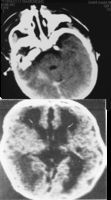

CT圖3.基底神經節大理石樣變性:基底節和丘腦出現大理石樣花紋。鏡檢神經元大量脫失、神經膠質增生,並有髓鞘過度形成。臨床上表現錐體外系功能失調,手足徐動與此有關。為缺氧性腦損傷。

苯巴比妥鈉(四)中樞神經系統興奮藥等:可用細胞色素C三磷酸脲苷輔酶A等每日靜脈滴注直至症狀明顯好轉;也可使用胞二磷膽鹼100-125mg/日稀釋後靜點生後第2日開始每日一次靜滴;腦活素5ml以生理鹽水稀釋後靜滴均可改善腦組織代謝治療必須持續至症狀完全消失中度HIE應治療10-14日重度HIE應治療14-21日或更長治療開始得愈早愈好一般應在生後24小時內即開始治療儘量避免生後各種病理因素加重腦損傷七預後導致不良預後的一些因素有:①重度HIE;②出現腦幹症狀:如瞳孔和呼吸的改變;③頻繁驚厥發作藥物不能控制者治療一周后症狀仍未消失者④治療二周后腦電圖仍有中度以上改變⑤腦B超和腦CT有Ⅲ-Ⅳ級腦室內出血腦實質有大面積缺氧缺血性改變尤其在1-2周后出現囊腔空洞者